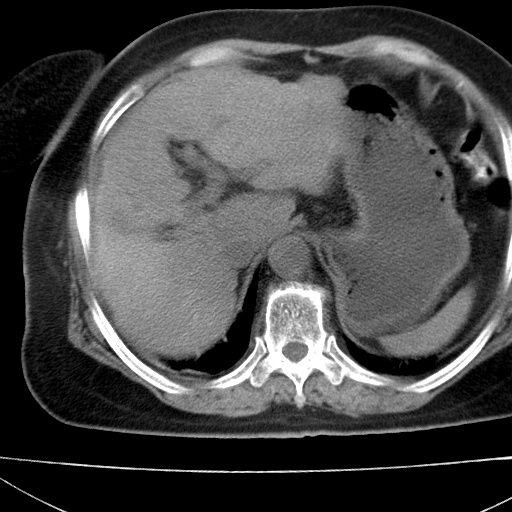

患者女74岁;右上腹胀痛1月,伴恶心,无发热;生活在疫水区。有术后病理及术后半年的追踪ct.

1)慢性血吸虫病(典型)。2)肝硬化。3)肝癌?4)胆囊炎。5)少量腹水。6)右侧少量胸腔积液。

支持.边缘见高密度线条样钙化影.

肝脏体积缩小,肝裂增宽,边缘不平呈波浪状,肝右叶见分隔状条索形钙化,亦见多结节低密度灶,边界不清,肝周可见少许液性暗区,胆囊增大内密度均匀,脾脏下缘低于脏脏的下缘,胸腔亦见液性暗区,余未见明显异常.

诊断:1肝硬化并慢性吸血虫病,脾肿大

2肝内占位,考虑肝癌可能性大,建议做增强

3胆囊炎, 4少量腹水及胸水

胆囊增大饱满,壁增厚。胆囊颈部见软组织密度影。临近肝右叶前段见片状低密度区,病灶下部见条状钙化,少量胸腹腔积液。意见:胆囊颈癌累及肝脏。

病人以胆囊癌手术的,病理结果为中分化腺癌。

现在看看肝右叶内圆形低密度影你们考虑什么呢?

肝内圆形低密度影考虑扩张的胆管

请看3mm重建像如下: